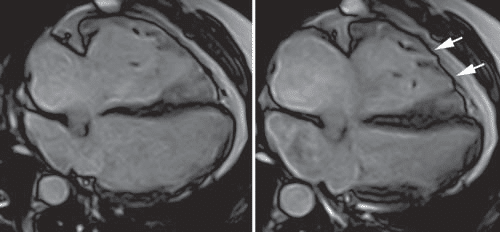

art13-5

Figure 5. Cardiac magnetic resonance, four chamber view in diastole (A) and systole (B), displaying an enlarged right ventricle, several microaneurysms at the mid and apical segments of the RV free wall (arrows).

After this extensive evaluation, the patient was lost to follow-up for almost 4 years, and came back for a routine evaluation in 2016. At present, the investigations included in the usual work-up of patients with ARVD (AC) suspicion were performed as recommended in the International Task Force consensus statements1,2. At this point, clear signs of disease progression  became apparent. The ECG displayed negative T waves from V1 through V6 and the inferior leads (DII, DIII, aVF), with a PVC with RBBB appearance, with a fragmented appearance of the QRS complex and low voltage QRS complex on peripheral leads (Figure 2).  The echocardiography revealed, apart from what was previously known, a pseudonormal fi lling pattern of the LV and a pathological average LVGLS of -12,7% (Figure 3). There was a more prominent involvement of the RV, which was enlarged (Figure 4) with global systolic dysfunction refl ected by a FAC of 22% and  with accompanying subtle WMA, mostly apical. The CMR examination confi rmed these fi ndings, exhibiting an enlarged RV (RVEDVI of 130 ml/m2) with a  pronounced systolic dysfunction (RVEF of 13%), with several microaneurysms at the mid-segments of the RV free wall and fi ne bands of fi brosis (Figure 4). There was a signifi cant progression of the disease concerning the LV, which displayed an EF of 37.5%, with multiple WMA, small apical aneurysm and localized fi brosis of the lateral wall. The 24-hour ECG monitoring,showedventricular premature contractions (750/24h), less than 4 years ago – most likely in response to optimization of therapy with beta-blockers. The ECG stress-test was unremarkable, with good  exercise tolerance and no arrhythmic events. The signal-averaged ECG (SAECG), which is a practical and widely available tool to helpAC diagnosis, was performed and our patient met 3 out of 3 criteria (Figure 5), only 1 out of 3 being necessary to count as a minor criteria. At this point, according to the revised 2010 TFC1 the diagnosis is unequivocal, with the fulfi llment of 2 major imaging criteria (enlarged RV with suggestive WMA described on both  echocardiography and CMR), 1 major ECG criteria (with inverted T waves in multiple leads) and several minor criteria, such as positive SAECG and over 500 PVCs on 24 hour rhythm monitoring. Nevertheless, the patient is completely asymptomatic, as he denies breathlessness, palpitations, syncope or chest pain. The patient was continued on an optimized beta-blocker dose (metoprolol succinate, 50 mg once daily). Seeing as he has several minor risk factors (proband, male gender, inverted T-waves in more than 3 precordial leads, fragmented QRS on ECG) and one major risk factor represented by moderate biventricular systolic dysfunction, the patient has a class IIafor ICD implantation based on expert consensus. Based on the 2015 ESC Guidelines on sudden death prevention3, in the absence of ventricular tachycardia, risk factors among which extensive RV disease, LV dysfunction  and late gadolinium enhancement on CMR (including